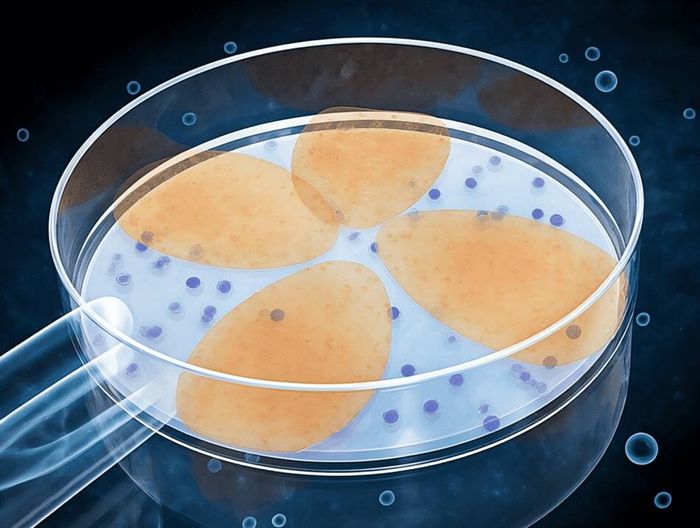

在医疗器械检测领域,生物相容性检测指通过细胞毒性、致敏、刺激等试验,评估材料与人体接触时的安全性,考察是否引发炎症、过敏等反应,是确保器械临床使用安全的关键检测。

其核心是依据相关标准,验证材料与人体组织的相容性,降低不良反应风险,为医疗器械的生物安全性评价提供科学依据。

3、分析检测

样品分析/检测,技术工程师开始制作分析汇总报告